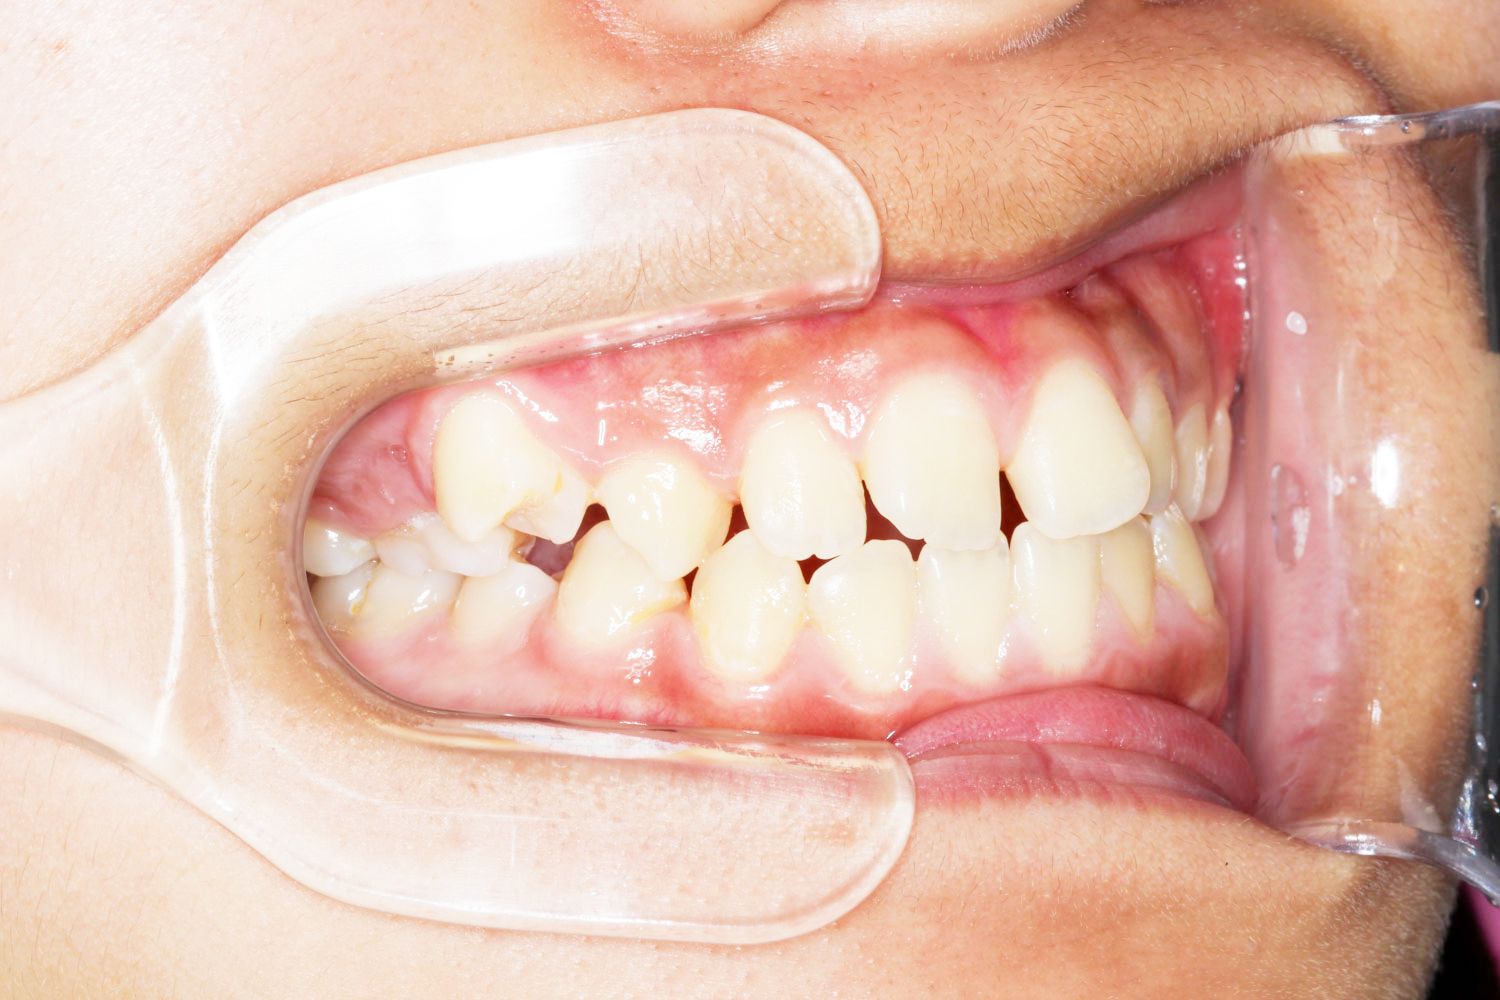

Before

年齢 10代

治療装置 上下とも裏側の矯正装置(フルリンガル)

治療内容 非抜歯

治療期間 2年8か月

リスク 歯の移動に伴う痛み、歯肉退縮、歯根吸収、歯肉炎、虫歯

主訴 八重歯が気になる

症状 叢生(ガタガタ)

治療回数 35回程度

総額費用 140万円程度